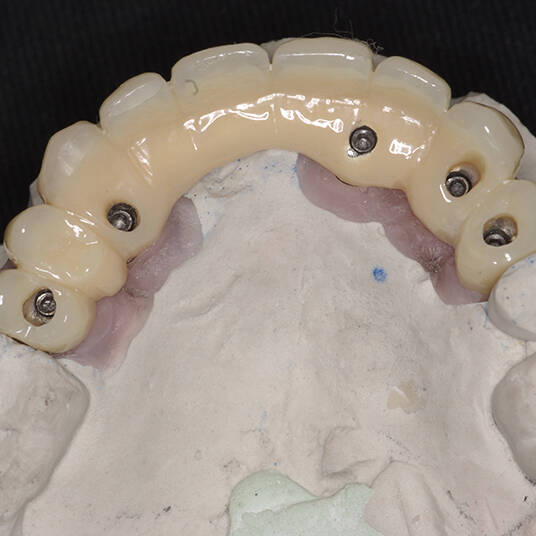

Utilizamos a tecnologia CAD CAM, um sistema avançado que possibilita a confecção precisa das próteses dentárias diretamente sobre os implantes. Esse método inovador garante um ajuste perfeito, um resultado estético superior e proporciona muito mais conforto e durabilidade. Com o CAD CAM, nossos pacientes contam com um processo mais rápido e previsível para alcançar o sorriso desejado.

Na Clínica Pontes Odontologia, somos referência em implantes dentários em Fortaleza, oferecendo tratamentos de alta qualidade e tecnologia de ponta. Os implantes dentários são estruturas de titânio posicionadas cirurgicamente no osso maxilar ou mandibular para substituir as raízes dos dentes ausentes. Essa técnica permite a fixação de próteses personalizadas, restaurando a função mastigatória, a estética e a autoestima dos nossos pacientes.